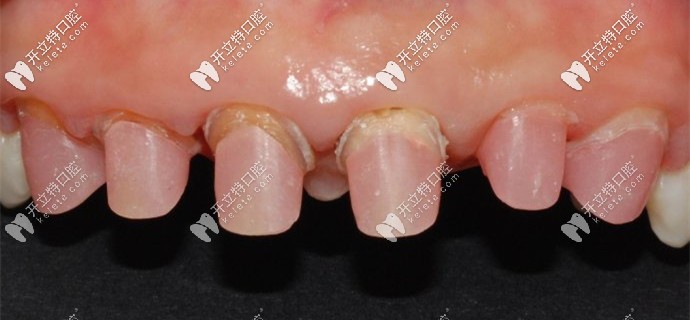

被磨掉1/2的基牙

牙醫(yī)說(shuō)我的牙齒情況不容樂(lè)觀,之前醫(yī)生操作不當(dāng)?shù)脑?,?dǎo)致牙槽骨萎縮、基牙腐爛,只能建議拔掉做種植牙。

我的基牙已經(jīng)腐爛了只能做種植牙